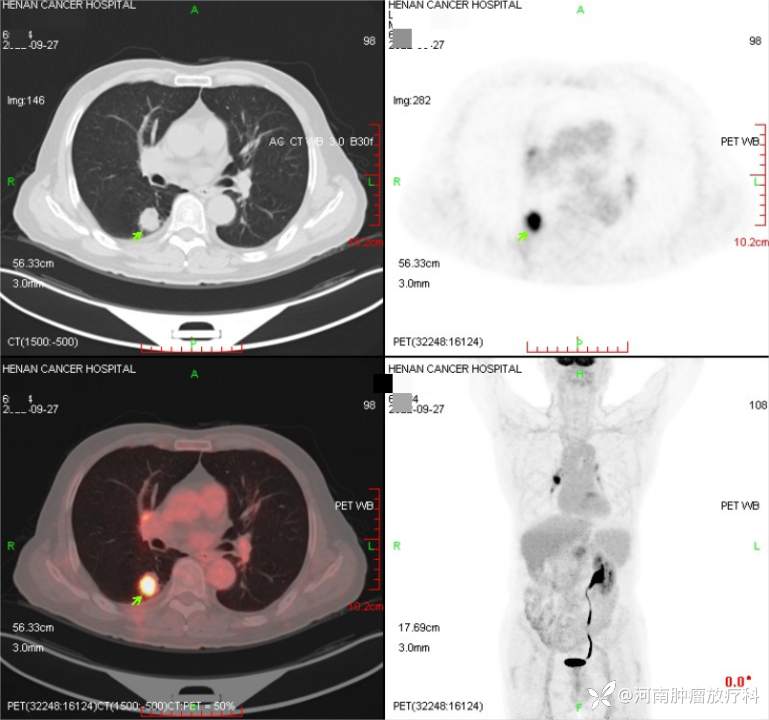

2022-9-27 PETCT

2022-9-26行CT引导下经皮肺穿刺活检,病理:(右肺)恶性肿瘤,伴神经内分泌表达,结合形态及免疫组化,符合:非小细胞肺癌,可疑大细胞神经内分泌癌。